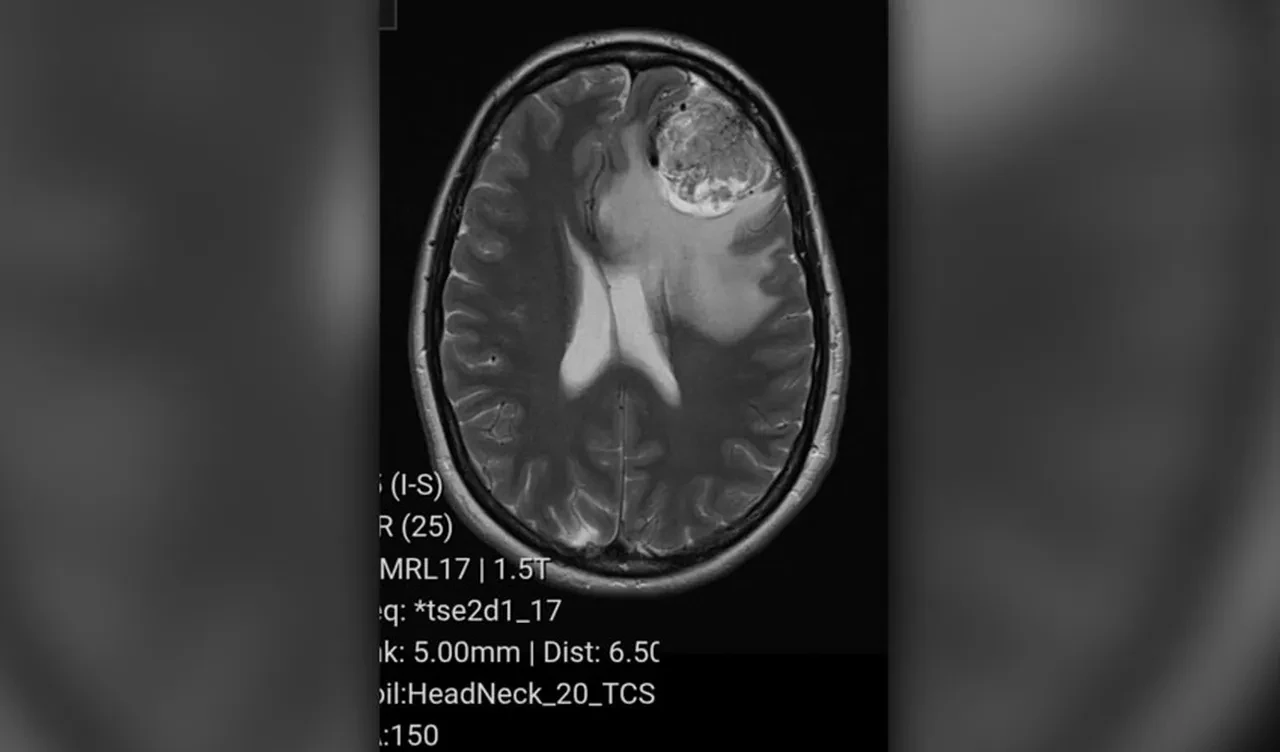

Ücretli olarak MRI taraması yaptıran Sterling, sonucu öğrendiğinde ise ''şoke oldum'' diyerek şaşkınlığını dile getirdi. Doktor, frontal lobunda 'büyük bir kitle' olduğunu yani kanserli olmayan bir beyin tümörü teşhis ettiğini aktardı.

Londra'daki King's College Hastanesi'ne sevk edilen Sterling, burada bir beyin cerrahının kendisine en iyi tedavi yolunun tümörün ameliyatla alınması olduğunu söylediğini anlattı. Sterling'in ameliyatı 4 saat sürdü. Doktorlar, tümörün 20 yıldır büyüyor olabileceğini söyledi.